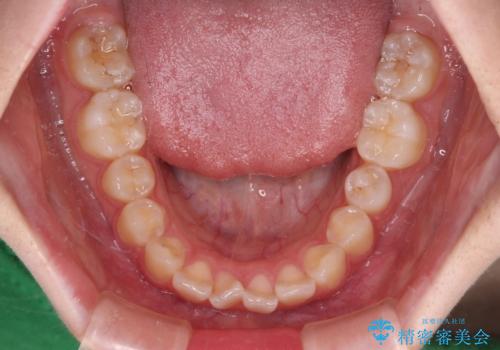

- 上下前歯のねじれを気にして来院された患者様です。

ワイヤー矯正でもマウスピース矯正でも対応可能でしたが、マウスピース矯正の自己管理が面倒であること、上顎前歯の捻転が著しいことから、ワイヤー矯正での治療を希望されました。